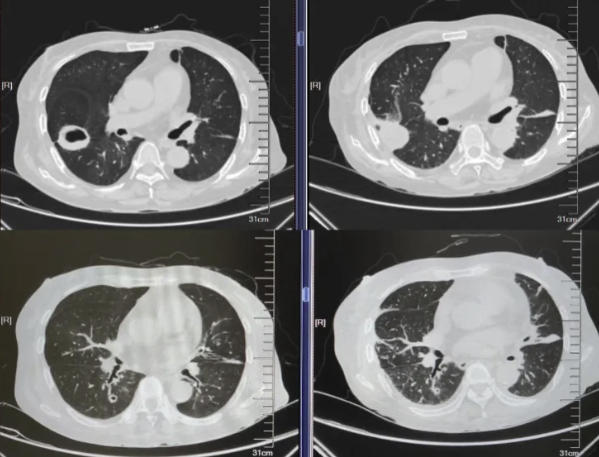

- 胸部CT(图1)(2025-8-15):1、右肺上叶后段空洞性病变(壁厚薄不均,长径约4.9cm,边界尚清,部分边缘稍欠毛糙),双肺多发结节(多发实性、磨玻璃密度结节影,界清,最大者位于右肺下叶背段,长径约1cm,内见空洞),建议CT增强进一步检查。 2、双肺散在炎症、纤维灶;双侧部分支气管轻度扩张;右肺上叶肺大泡。 3、心包部分增厚;主动脉、冠脉多发钙化。 4、腰1椎体楔形压缩。 5、所示双肾形态不规则。

图1.胸部CT(2025-8-15)

2025年8月31日,患者进食后出现严重恶心、呕吐等胃肠道反应,伴肝酶升高,经予止吐、护胃、静脉营养支持及保肝治疗后未见好转,考虑为复方磺胺甲噁唑片不良反应,遂将其剂量逐步减量至0.48g bid后患者胃肠道反应减轻。2025年9月1日复查血液指标提示BNP及D-二聚体升高,加用利尿、抗凝等对症治疗;复查胸部CT(见图4)显示右肺上叶空洞性病变及右肺下叶背段结节较2025年8月15日影像明显缩小,提示当前抗感染治疗方案有效。

本例患者经约1周抗毛霉治疗后复查胸部CT,提示肺部病灶较前明显缩小,血沉、CRP等炎症指标亦较前下降,提示初始治疗有效。在患者病情趋于稳定后,将静脉抗真菌治疗转换为口服序贯治疗,可选药物包括艾沙康唑或泊沙康唑。鉴于患者肾小球滤过率偏低,我们于2025年9月15日起选用艾沙康唑进行口服序贯治疗。同时嘱患者积极控制危险因素,逐步减量并最终停用糖皮质激素,严格调控血糖。1个月后复查胸部CT(见图9)显示右肺病灶持续缩小、空洞消失;实验室检查提示白细胞、CRP、血沉、降钙素原及IL-6均恢复至正常范围,G试验转为阴性。目前患者继续定期随访,监测影像学及血液学指标。

图9.胸部CT(25-8-15 vs 25-9-1 vs 25-10-13)